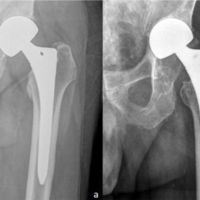

This case report involves a 49-year-old lady who is a biopsy-proven case of triple-negative mammary invasive carcinoma of the left breast and underwent a left mastectomy in 2018. Following which she was on eight cycles of chemotherapy, followed by radiotherapy and hormonal therapy. Two years following mastectomy 1 day while she was on her way for chemotherapy she had a trivial injury to her right hip. She was not able to ambulate post-injury. She came to us with complaints of right hip pain. On examination, she had tenderness over the Scarpa’s triangle and painful hip movements. Endocrinology workup was done which showed reduced serum calcium and elevated serum phosphorous and alkaline phosphatase levels. Radiographs revealed an undisplaced subcapital fracture of the right femoral neck (Fig. 1). Magnetic resonance imaging (MRI) of the spine showed heterointense lesions involving the entire spine in T1/T2 and STIR images (Fig. 2a). MRI also revealed osteolytic lesions in the contralateral neck of femur (Fig. 2b). Positron Emission Tomography scan was suggestive of extensive skeletal metastasis involving the entire axial skeletal system, bilateral humerus, ribs, bilateral scapula, and bilateral proximal femur (Fig. 3a and b). After a thorough review of the literature and assessing all possible options of intervention, the patient underwent right hip bipolar uncemented hemiarthroplasty following an anesthetic workup (Fig. 4). The femoral head was sent for histopathological examination. Intraoperative biopsy revealed fragments of bony trabeculae enclosing suppressed marrow elements and fat infiltrated by a tumor composed of singled-out cells which are eosinophilic in nature with peripherally pushed hyperchromatic nucleus showing atypia and mitosis (Fig. 5). Thus confirming the metastatic spread to the femoral head. Postoperatively, patient was advised strict bed rest and was not allowed to weight bear post-procedure. The patient was regularly followed up 2 weeks, 4 weeks, and 6 weeks post-procedure. Forty-five days post-procedure, subsequently patient had another episode of trivial injury to her left hip. She was worked up again through the same protocols and she diagnosed with a transcervical undisplaced left neck of femur fracture (Fig. 6). Patient again underwent bipolar uncemented hemiarthroplasty in the contralateral hip (Fig. 7). The patient was followed up in regular intervals. There was no periprosthetic joint infection, loosening of femoral stem, periprosthetic fractures or dislocation in the post-operative period. At 3 months, follow-up functional and radiological outcomes were assessed and were satisfactory. However, patient had another trivial injury to her left humerus which revealed undisplaced fracture of humeral shaft (Fig. 8). We did not want to operate her due to increased risk of perioperative cardiac and neurological worsening of patient. Henceforth, she was managed conservatively with custom-made thermoplastic splint. She was again followed up serially and the fracture healed well without any functional compromise (Fig. 9).